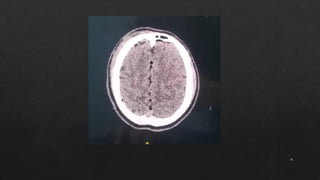

CT scan kepala 3/8/24

- Perdarahan epidural di regio frontal kanan dengan ketebalan maksimum 3 mm.

- Multipel fraktur komplit os frontal yang mencapai dinding lateral-posterior

sinus frontalis kanan, dinding medial-posterior orbita kanan dan lamina

papyracea yang mencapai sinus ethmoid kanan-kiri, sinus maksillaris kiri, dan

sinus sphenoid kanan, dan dinding inferior orbita kanan yang mencapai sinus

maksillaris kanan.

- Multipel pneumoencephali ekstraaksial di sekitar falx dan kedua hemisfer

cerebri terutama regio frontal bilateral.

- Subgaleal hematoma regio frontal kanan dengan ketebalan maksimum 6 mm.

- Defek dan edema jaringan lunak periorbita kanan, dan labia superior

- Panhematosinus.

- Dilatasi ruang subarachnoid di fossa temporal kiri, suspek kista arachnoid.